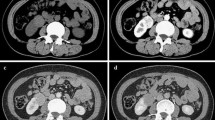

All models predicting malignancy revealed a statistically significant outcomes (p < 0.001, for all). Although the AUC of the ROC curve showed no statistically significant difference (p > 0.05, for all), the highest AUC of the ROC curve was observed in Model 2 which included PAI (Table 3 & Fig. 1). No significant difference was found in PAI between the Fuhrman grades (p > 0.05).